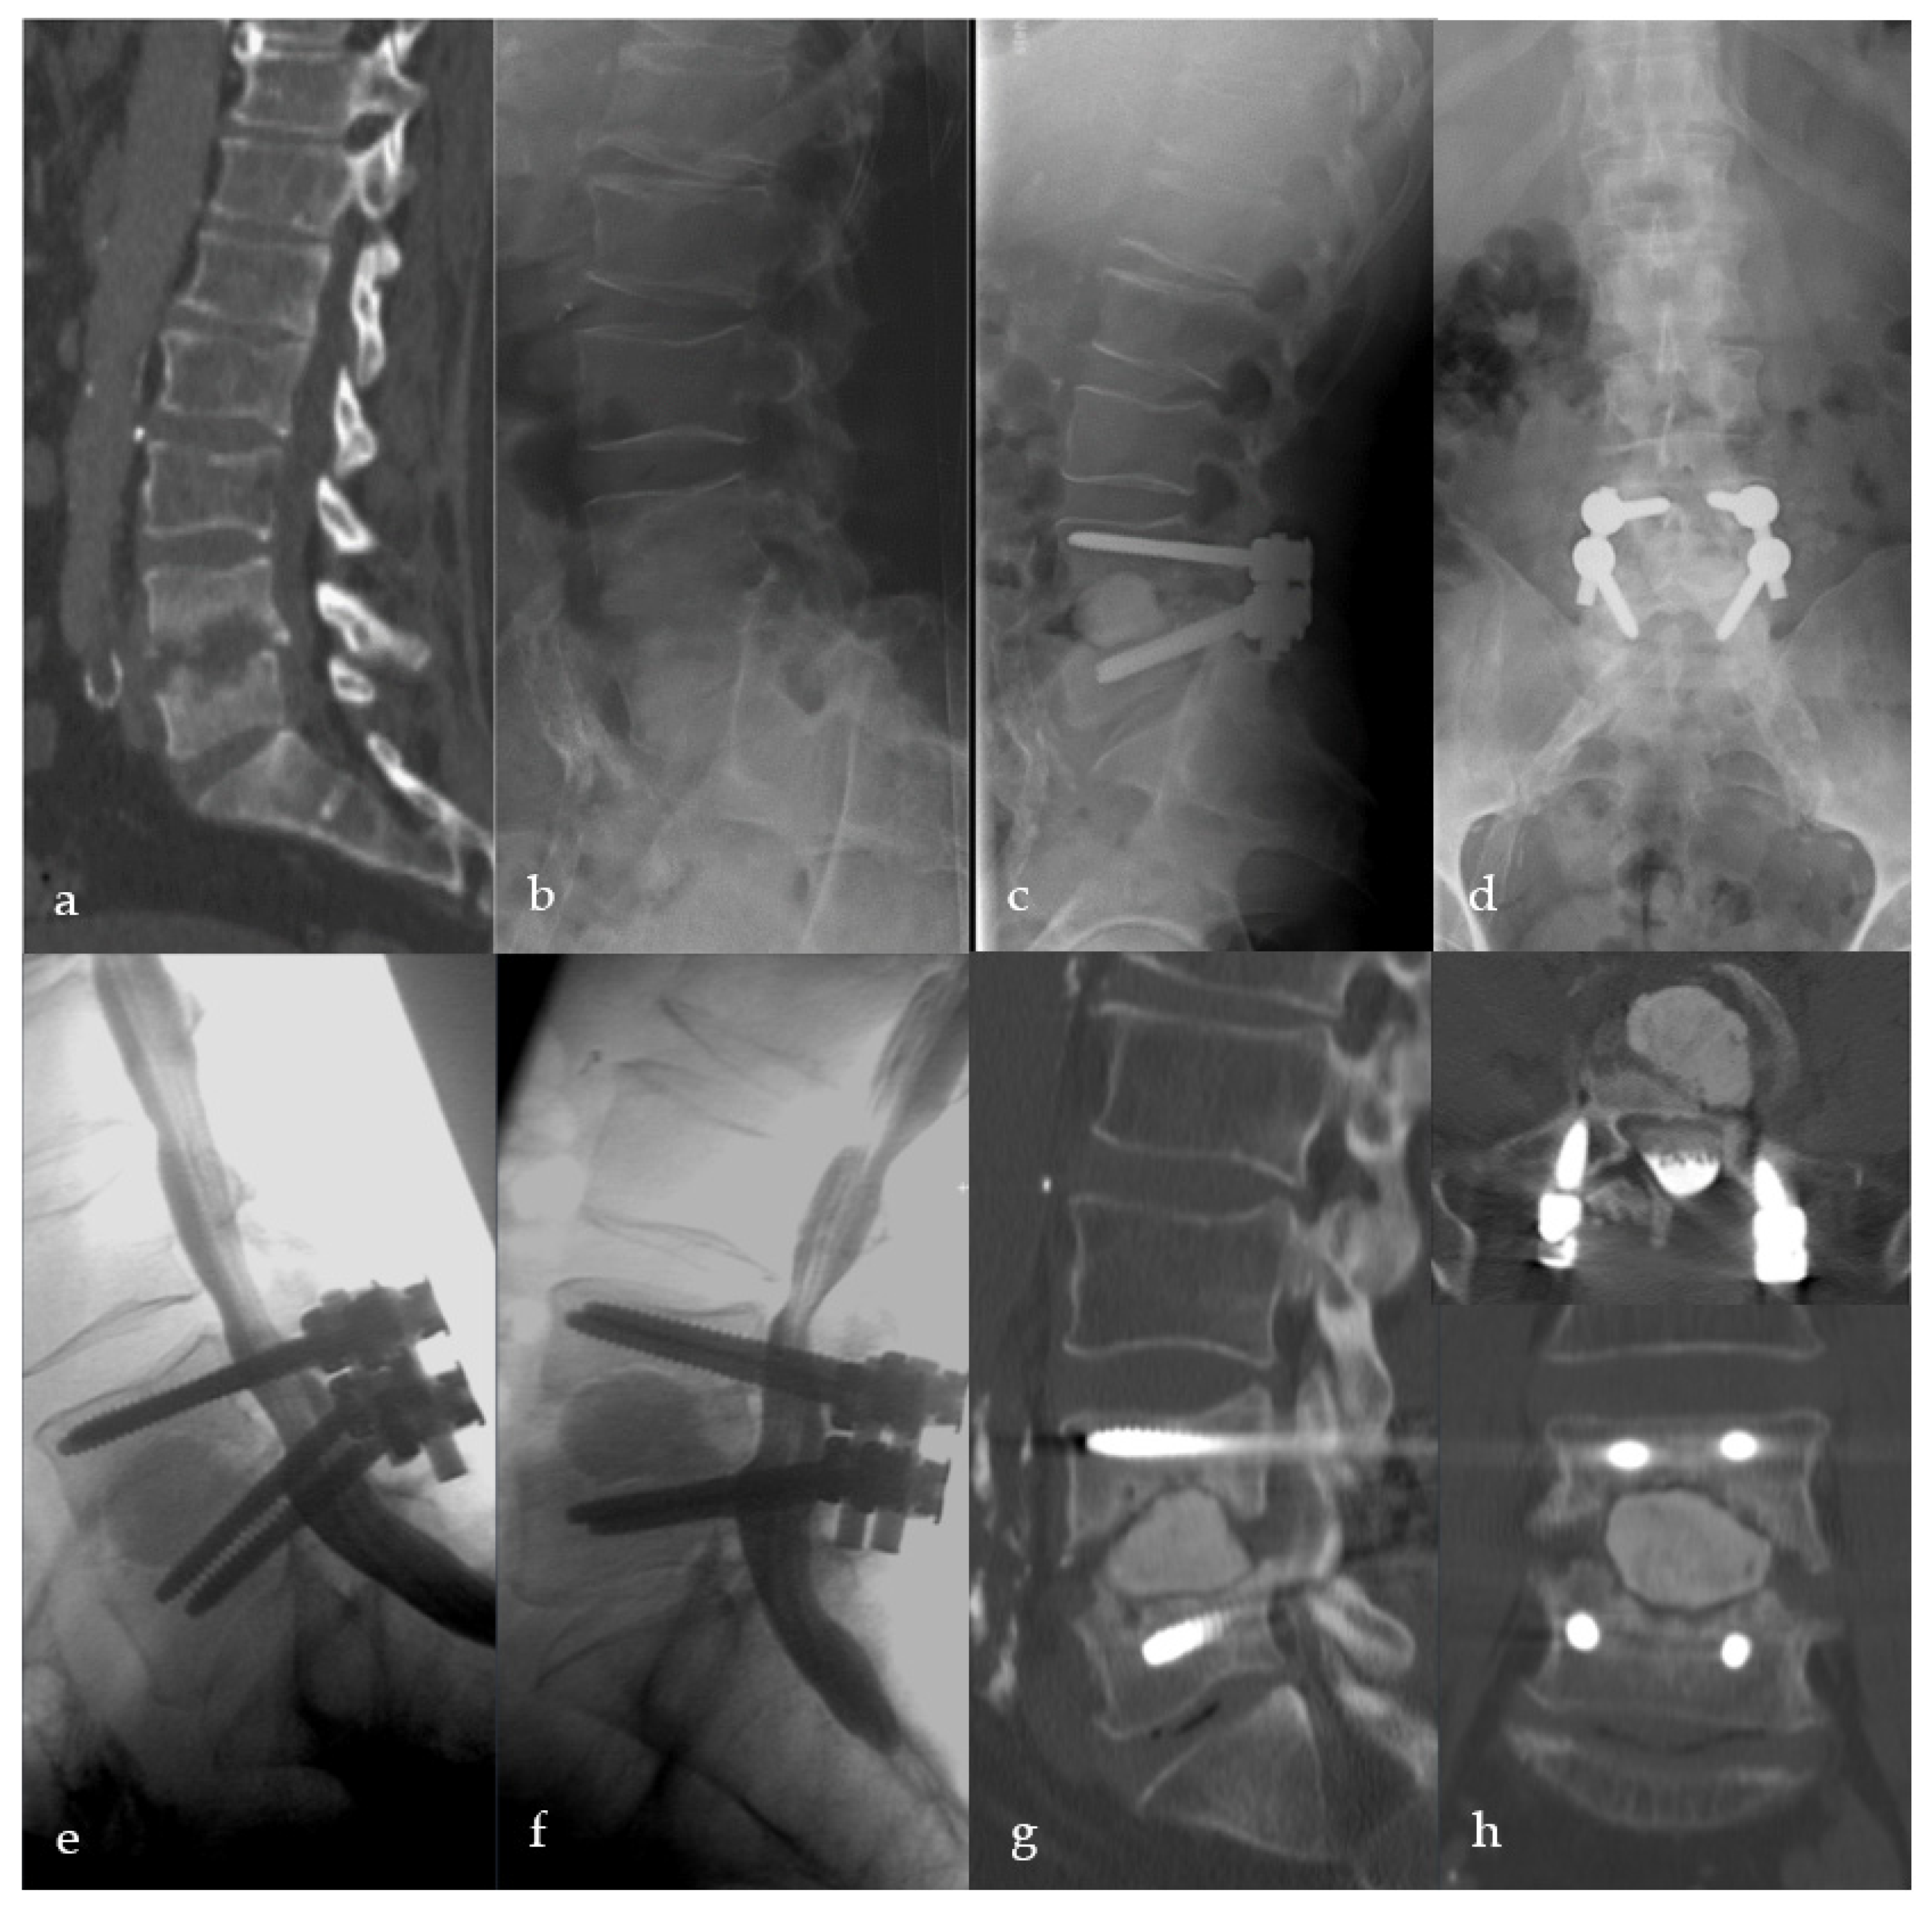

2.2. Surgical Procedure